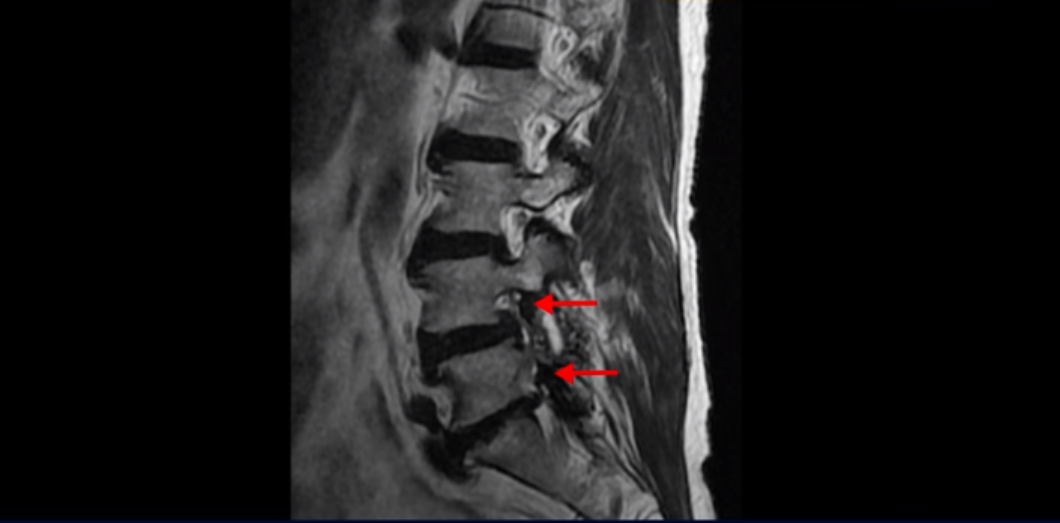

MRI를 보면 척추 여러 마디가 퇴행되어 있고

척추관도 좁아져 있고

특히 왼쪽 신경가지가 빠져나가는 4번 5번, 5번 1번 추간공들이 많이 좁아져 있습니다.

그래서 이분은 몇 달 전부터 갑자기 왼쪽 엉덩이부터 발바닥까지 저리고 아픈 증상이 생겨서 걷기도 어렵고 무릎도 차고 시립니다. 그런데 왜 이렇게 얼마 전에 갑자기 발병한 협착증일수록 치료가 정말 빠르고 쉽다는 걸까요?